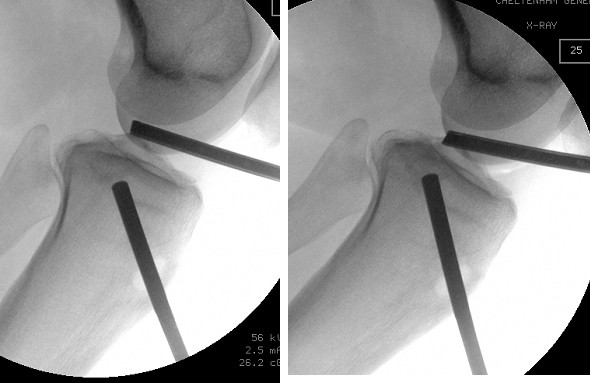

The subtle depressed fractures can be treated arthroscopically with percutaneous placement of screws.